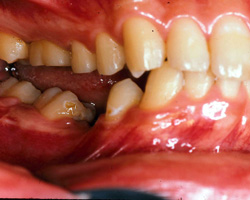

今回、この患者様のスプリント調整は、装着時から三回までは一週間ごと、四回から七回までは三週間ことのを三カ月かけて調整。その後、スプリントを再製作し装着、以降三カ月に一度の調整を二年間線り返しました。写真3) 4) 5) 6)はその時の状態です。臼歯部が大きく離閉じているのがおわかりかと思いますが、この隙間が頭蓋骨の歪み、頚椎の歪みが咬合面上に現れた状態で、決して歯牙が歯槽骨内に埋入したわけではありません。

| 写真3)2年後の状態 | 写真4)スプリントをはずした時の状態(右側) |